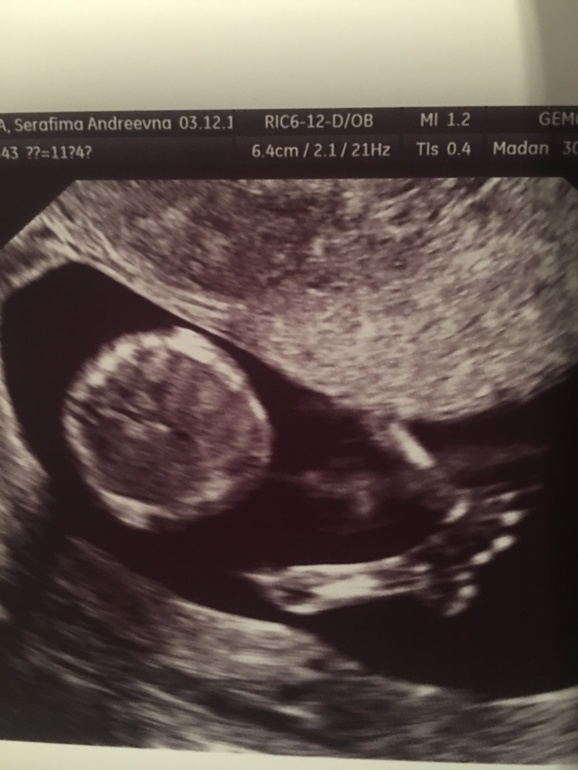

Тадааам у нас девушка!!

Сказали что стрелочки не видно, а видно два лепестка и дали 70% что девочка растет!

Потом затихла и нужно было чтобы перевернулась, на нее надавили и она как давай кувыркаться) шоу такое устроила!пуповина позволяет! Это так мило! Я пишу неинформативный пост! Простите)